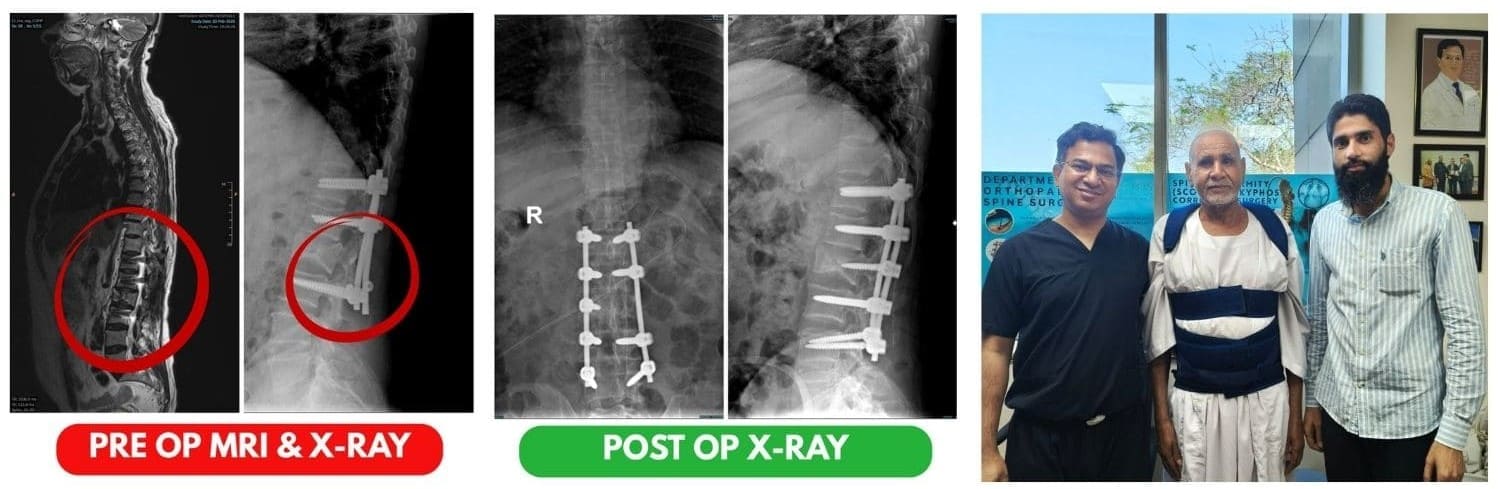

Successful Revision Spine Surgery in India : Restoring Mobility and Nerve Function

A 64-year-old male patient visited Artemis Hospital seeking expert treatment for severe spinal complications that developed after a previously performed spine surgery. […]